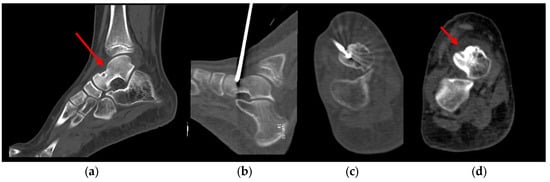

2.2. Procedure